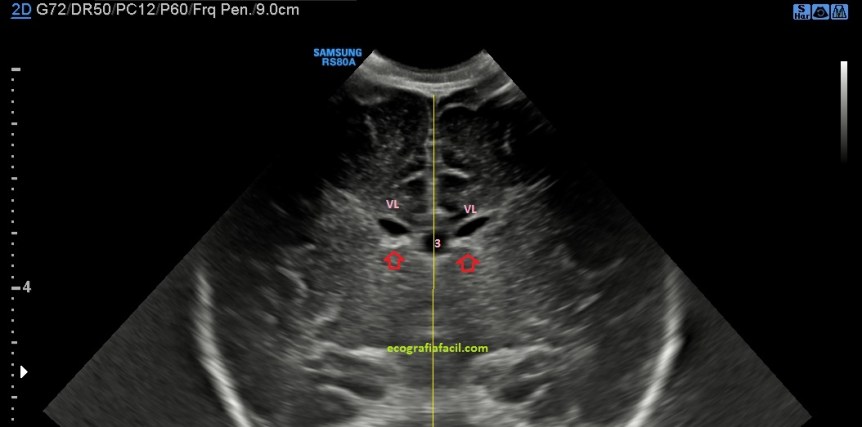

La ecografía mostró una tumoración en la región del cordón espermático derecho de unos 4cms, siendo una lesión sólida,hipoecogénica, muy bien delimitada y moderadamente vascularizada en el Doppler color.

Lo que vimos fue una masa sólida no móvil con la descripción semiológica explicada con anterioridad.

Siguiendo el protocolo habitual lo que hacemos es medir el hallazgo en los tres ejes del espacio.